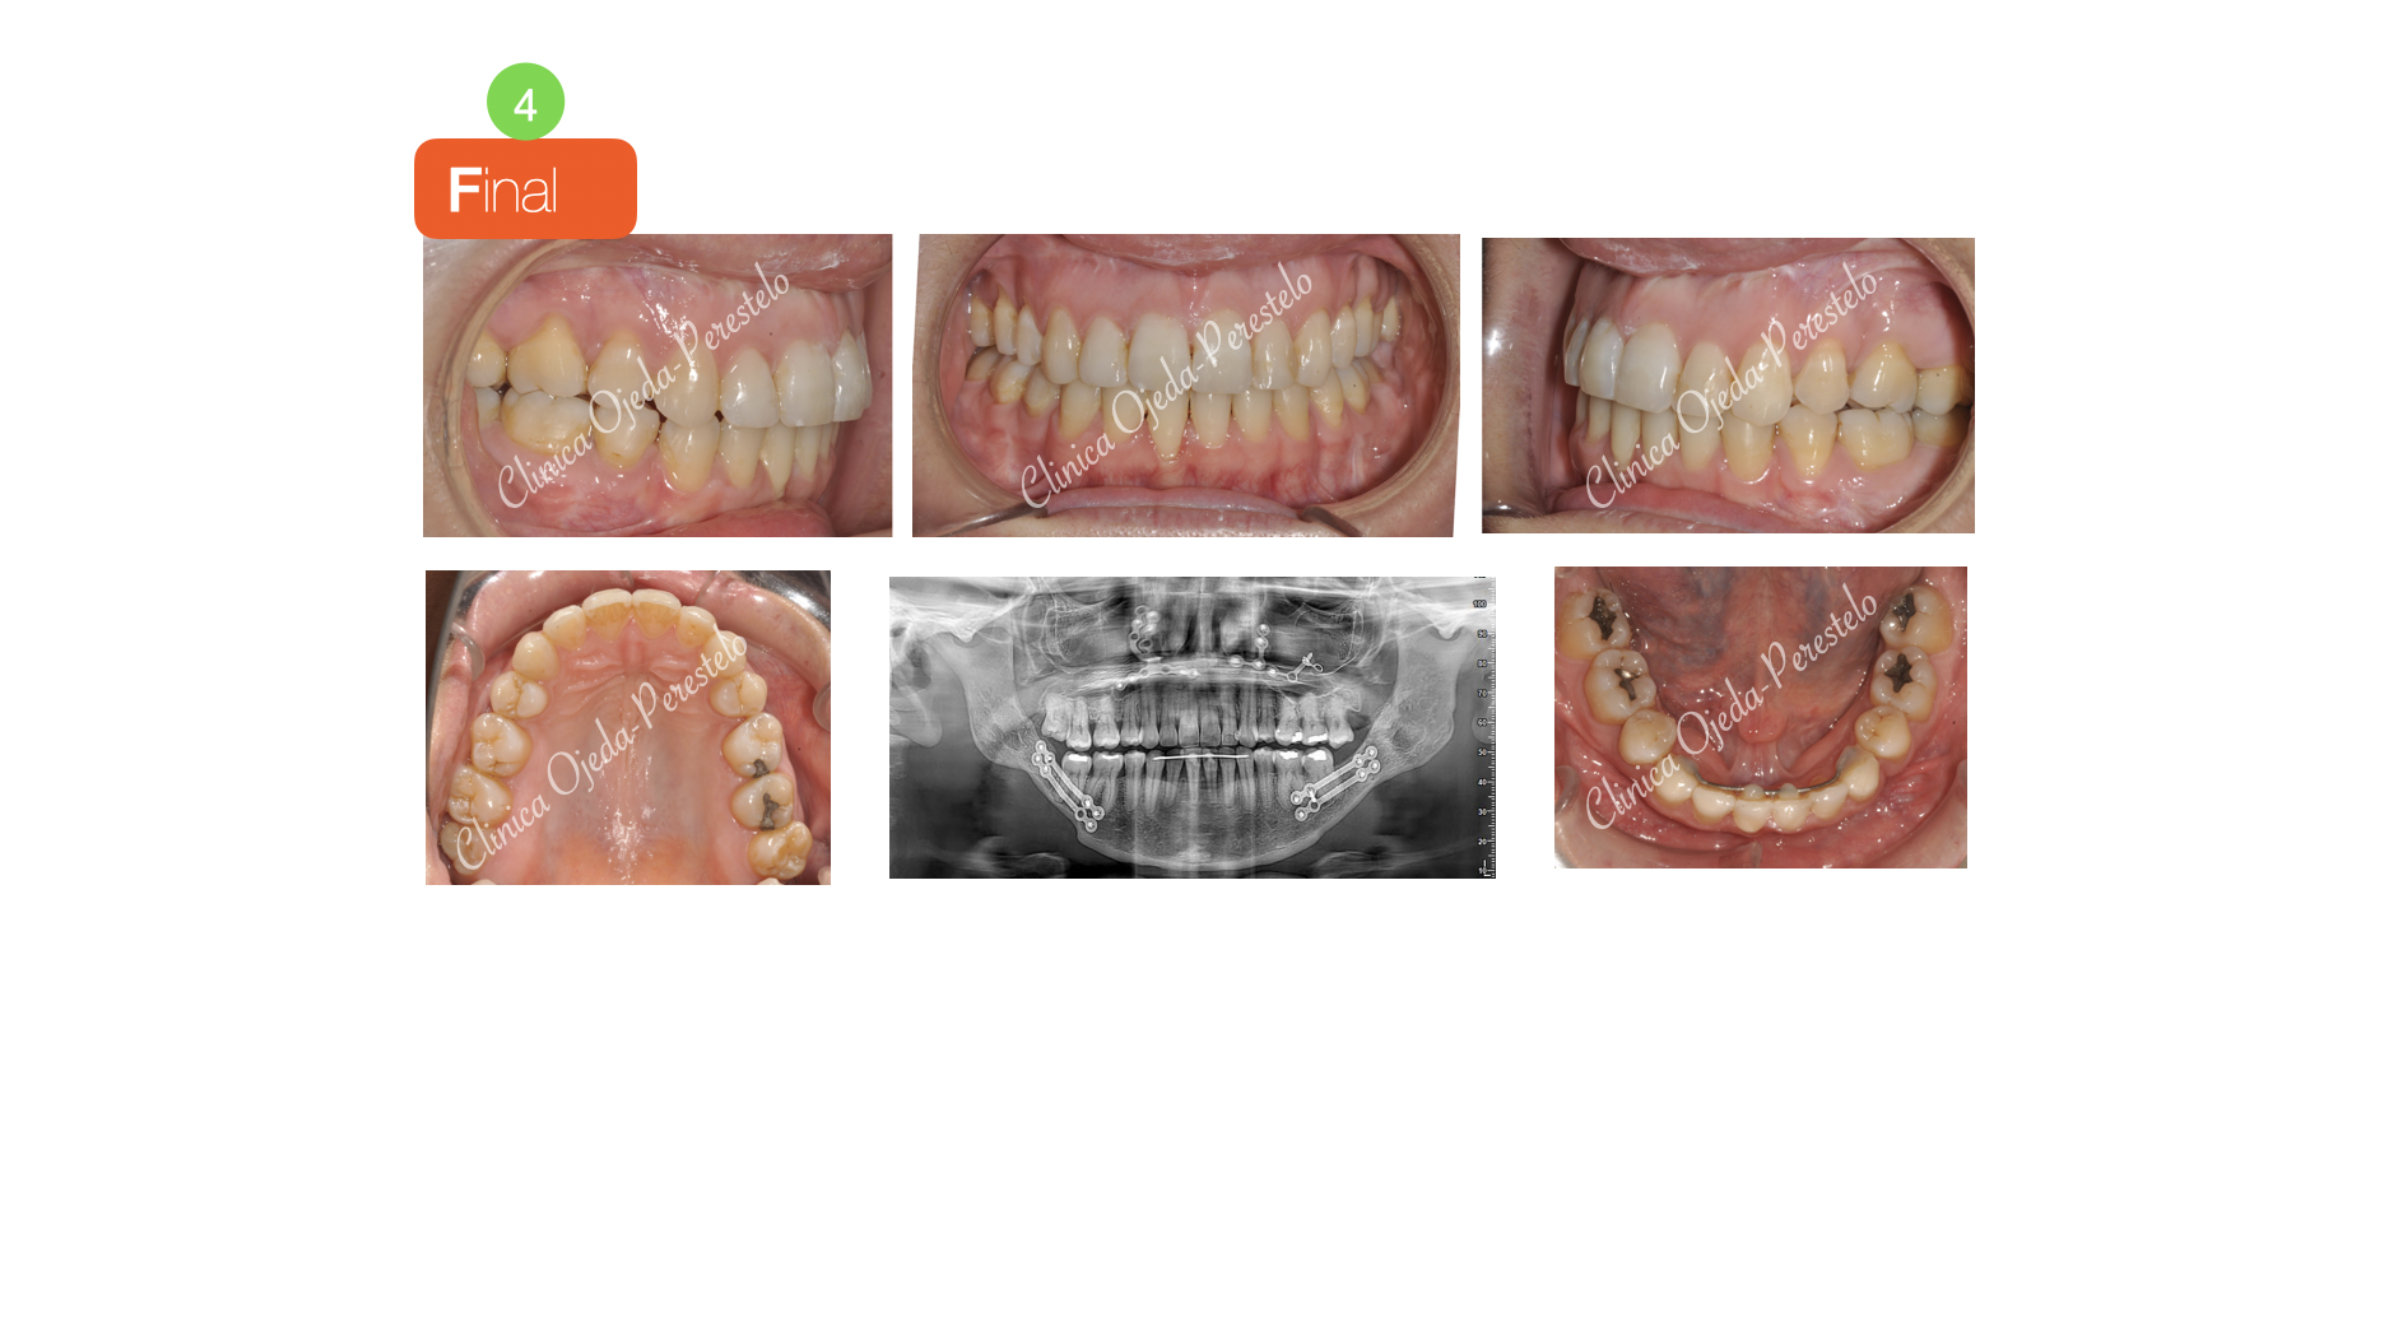

Quisiéramos destacar la mejora en la sonrisa y en la calidad del sueño experimentada por la paciente. Su perfil y su competencia labial ha mejorado de manera considerable, pudiendo la paciente respirar a boca cerrada. Presentamos la estabilidad del caso a 7 años.